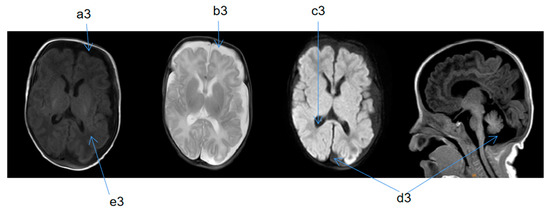

| Cranial MRI abnormalities | + | + | + | + | + |